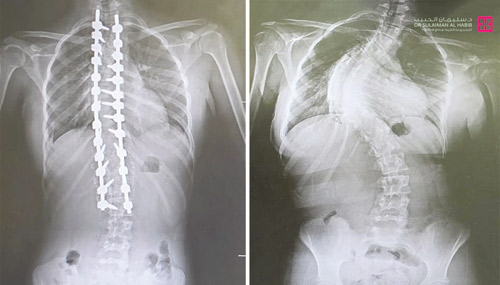

مستشفى الدكتور سليمان الحبيب بالقصيم يجري عملية ناجحة لتقويم «جنف»

أجرى مستشفى الدكتور سليمان الحبيب بالقصيم، عملية جراحية معقدة، لتقويم انحراف متزايد في العمود الفقري «جنف»، وتثبيت ودمج الفقرات لفتاة، وأنهت العملية التي استمرت «7» ساعات، معاناة الفتاة مع عدة أعراض حادة استمرت معها لفترة طويلة. وقاد الفريق الطبي المعالج د. ناجي مسعود استشاري جراحة المخ والأعصاب والعمود